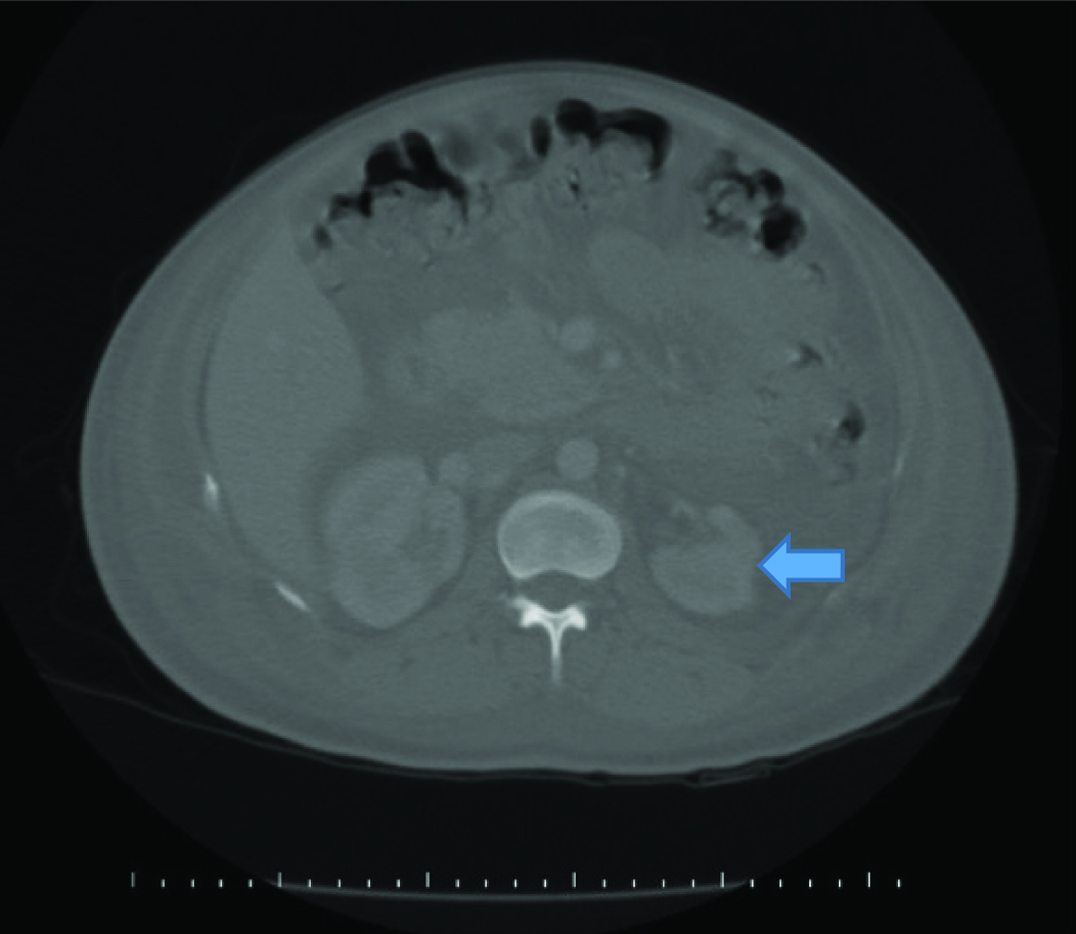

A 27-year-old primigravid female was referred to our clinic with severe preeclampsia at 35 weeks of gestation. Her medical history was uneventful. She was administered 1000 mg/day alpha-methyldopa since, 28 weeks of gestation. On admission, her blood pressure was 180/ 110 mmHg and urinary albumin 2+. Complete Blood Count (CBC) was in normal limits. Her serum biochemical analysis revealed: ALT: 401 U/L, AST: 292 U/L, creatinine: 1.39 mg/dL, urea: 40 mg/dL (16.6-48.5), uric acid: 8 mg/dL (2.4-5.7), total protein: 6.25 g/dL (6.4-8.3) and albumin: 3.3 g/dL (3.5-5.2). Her coagulation profile was within normal limits. A single live fetus of 31 weeks gestation along with 85 mm amniotic fluid index was detected by USG. Colour flow doppler USG revealed increased umbilical artery resistance. There were no subjective symptoms such as headache, epigastric pain and visual symptoms. Late decelerations were detected on cardiotocography trace and she was diagnosed to have fetal distress. An emergency cesarean section was performed and 1450 gm male fetus was delivered with APGAR score of 8/10. Postoperatively, she was given amlodipine 20 mg/day. Her blood pressure recordings were within normal limits. On first postoperative day 20-30 cc/hour urine output was detected. Serum transaminases were lowered. On the second postoperative day, she had abdominal distension and severe abdominal pain. The USG showed minimal ascites fluid. CBC was normal and serum albumin level was 2.5 gm/dl. Serum sodium level was normal. She had 320 μg albumin/mg creatinine (albumin:creatinine ratio) on spot urine sample. On the 3rd post-operative day, her abdominal distension increased and USG revealed massive ascites. Abdominal drainage was performed and albumin infusion was administered. Approximately 3000 cc serous fluid was drained. The sample analysis revealed as characteristic of transudate. Abdominal distension regressed but she had pulse of 130/min. X-ray chest showed bilateral minimal pleural effusion [Table/Fig-1]. She had normal echocardiography. Serum creatinine levels regressed (<1 mg/dL) but her urine output exceeded 500 cc/hour. IV hydration was adjusted as less than 1000 cc of total daily urine output. On post-operative day 4, she still had abdominal distension and concomitant respiratory distress. Computed Tomography showed bilateral pleural effusion and minimal ascites and atrophic right kidney [Table/Fig-2,3]. In spite of increased urine output her sodium level remained within normal levels. There was no proteinuria in spot urine sample. On post-operative day 5, she had total of 3000 cc/day hydration and 5000 cc/day urine output. Her complaint regressed on the following days and on post-operative day 7 USG showed no ascites and gap between input and output disappeared. She was discharged on postoperative day 10.

Computed tomography, atrophic right kidney.